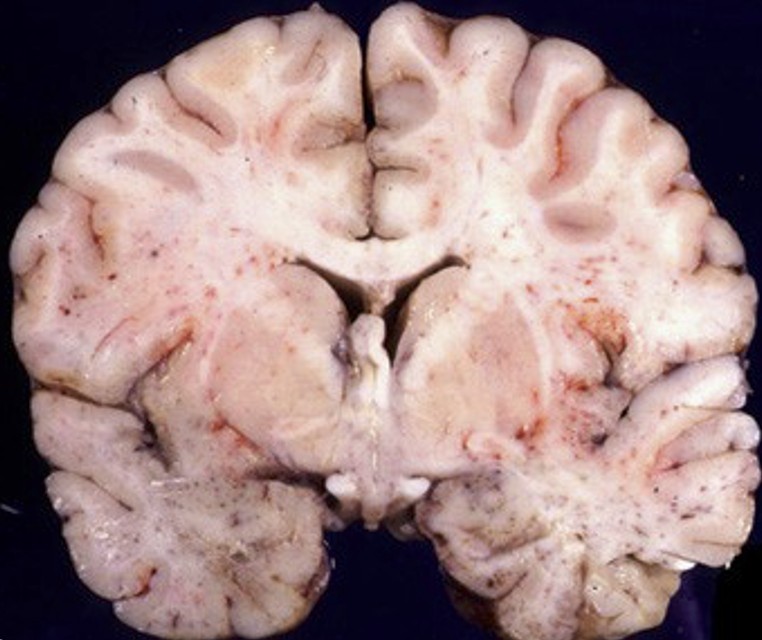

gross appearance of cerebral malaria ,

Describe what is seen

A

petechial hemorrhage in white matter

Q

Low power view of brain with malaria , identify what is seen

ring haemorrages

the pathology seen in the shown image is caused by

obstructed blood vessels in P. falciparum infection